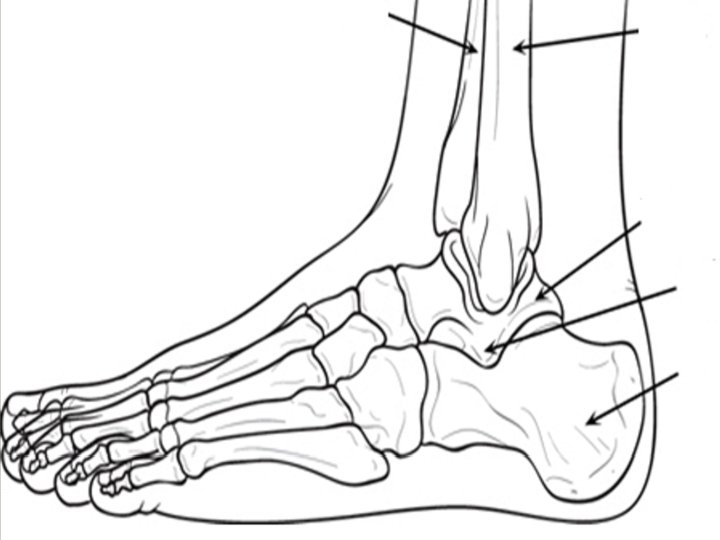

Anatomy Bones • Tarsals Calcaneus Talus Metatarsals Phalanges

Terms to Help You Tibio = Tibia Fibular = Fibula Talo = Talus Calcaneo = Calcaneus Phalangeal = Phalanges Break down the words on the upcoming slides! Don’t panic!!! Anterior = Posterior = Lateral = Medial = Superior = Inferior = Sub =

Foot and Ankle Articulations • Tibiotalar (ankle joint) Allows plantar and dorsiflexion • Subtalar Joint between talus and calcaneus Allows inversion and eversion • Midfoot – where tarsals meet metatarsals • Metatarsal Phalengeal (MP) Allows toe flexion and extension • Interphalengeal (PIP & DIP) Allows flexion and extension of toe segments

Ligaments of the Ankle Anterior Inferior Tibiofibular Ligament • Resists forced dorsiflexion and rotation of talus Posterior Inferior Tibiofibular Ligament Deltoid Ligament • Resists eversion

Ligaments of the Ankle Anterior Talofibular Ligament • Resists plantarflexion and inversion Posterior Talofibular Ligament Calcaneofibular Ligament

Soft Tissues Tendons Achilles Tendon – attaches the calf muscles to the calcaneus